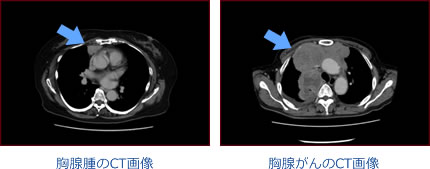

奇形腫

奇形腫が肺に穿破したCT画像

良性の腫瘍ですが、腫瘍が破れて、肺に穿孔して腫瘍の内容物が肺に侵入することがあります。このため、重篤な症状を引き起こしてしまうこともあります。